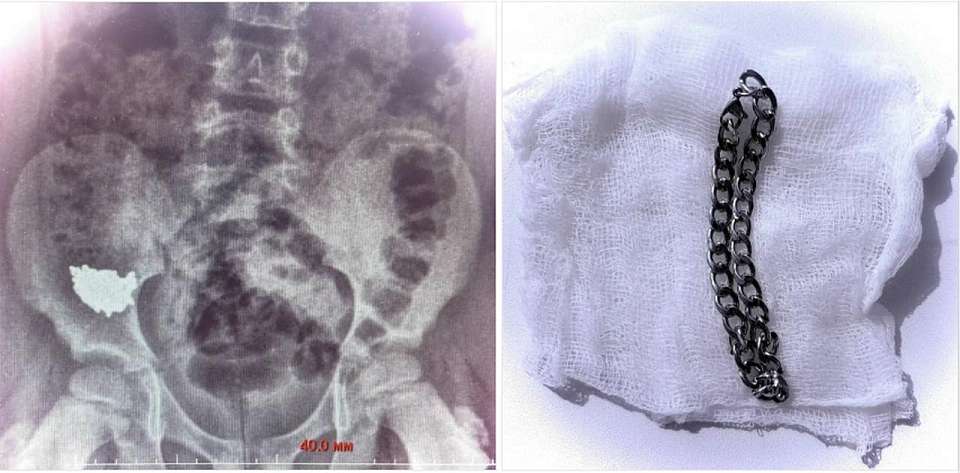

В ходе операции, проведённой под общим наркозом, врачи сначала выполнили колоноскопию, но цепочка обнаружена не была. Затем, проведя ревизию брюшной полости, медики обнаружили инородное тело и извлекли его через просвет аппендикса, завершив операцию аппендэктомией.